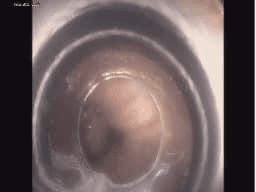

Thực hiện Điện tim, Siêu âm Doppler tim, Đo chức năng hô hấp, Tiêm nội khớp và phần mềm quanh khớp, Nội soi dạ dày tá tràng, nội soi đại tràng toàn bộ, thực hiện nội soi can thiệp đường tiêu hóa như: Nội soi can thiệp cầm máu, thắt giãn tĩnh mạch thực quản, cắt polyp dạ dày đại trực tràng…

HÌNH ẢNH GIỚI THIỆU VỀ KHOA: